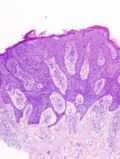

Bowen disease

Bowen disease is squamous cell carcinoma in situ of the skin.

- Its histomorphologic appearance may be similar to Paget disease of the breast/Extramammary Paget disease, Toker cell hyperplasia and melanoma.

- IHC is used to separate the entities definitively.

Micro

The sections show hair bearing skin. The squamous epithelium has full thickness changes including an increased nuclear-cytoplasmic ratio, loss of polarity, and nuclear hyperchromasia. Mitoses are seen in the upper third of the epithelium. Nucleoli are not apparent. No atypical cells are seen in the dermis. Parakeratosis overlies the abnormal keratinocytes. Solar elastosis is present. No melanocytic nests are identified.